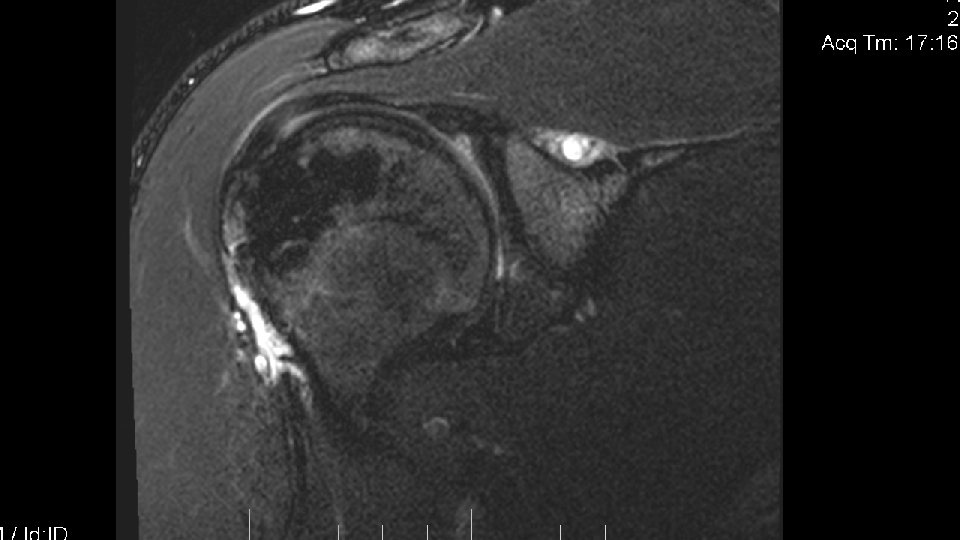

Patient History • This 21 yo male All-American Rugby player and a former High School state champion wrestler presented on Dec 4, 2015 for evaluation of generalized right shoulder pain. There was no history, past or present, of a specific shoulder injury, but the athlete had recreationally wrestled a few nights before and lifted weights prior to his visit. He complained of a dead arm sensation of his right arm and generalized discomfort globally in the shoulder. Motion was limited secondary to pain but no focal muscle weakness was present. The patient had a positive Hawkins, a positive O’Brien’s test thumb up and thumb down, a positive apprehension sign, and no gleno-humeral laxity. The patient was given diclofenac and scheduled for follow-up.

Follow up • The patient returned for follow up after Christmas Break. Generally, he was better. He had begun weight lifting at home but noticed the pain returning at a different location: his posterior scapular region. He also noted that he was weaker with certain motions. He denied any numbness, tingling or recurrent dead arm syndrome. Examination confirmed weakness to external shoulder rotation. Hawkins and O’Briens tests were unrevealing. No shoulder laxity identified in this heavily muscled athlete.

Disposition • The patient was scheduled for MRI